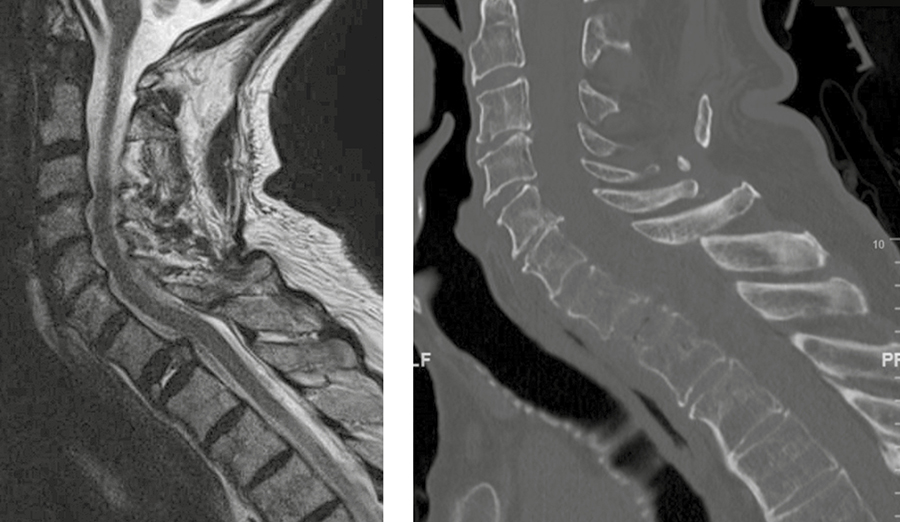

A 73-year-old man with a history of renal cell carcinoma presented with progressive bilateral upper extremity paresthesia/numbness, left upper extremity weakness, and upper back pain with a newly identified T1 pathological fracture (Fig 6).

The patient was taken to the operating room and underwent:

· Anterior T1 corpectomy and decompression of tumor and compressive material.

· Surgical reconstruction with DePuy Synthes SYNMESH cage and restoration of height. Given manubrium and angle of access, an anterior plate was not applied.

· C5-T3 posterior instrumentation with the DePuy Synthes SYMPHONY OCT System. Given the patient’s suboptimal bone quality, C5 and C6 lateral mass screws were reinforced with two MULTIPOINT SECURE screws placed bilaterally for an additional eight screws (Fig 7).